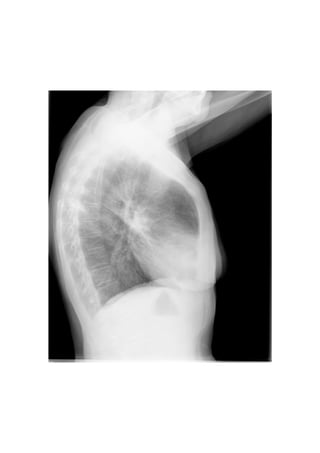

Este documento presenta 7 casos de patología torácica que serán discutidos en una sesión de interpretación radiológica. El objetivo es que los asistentes tomen notas aclaratorias durante la discusión interactiva de cada caso, en lugar de una mera explicación teórica. Los casos incluyen agenesia pulmonar derecha, situs inversus, estridor, neumonía con hemoptisis y enfermedad intersticial. El último caso involucra a un paciente de 86 años con tos y disnea que podría tener una consolidación en la base